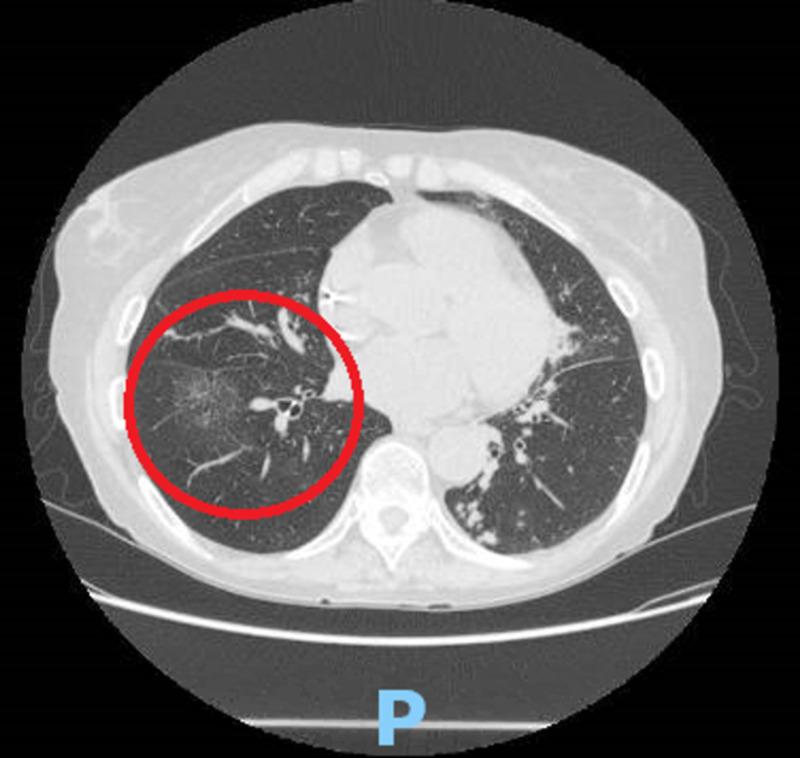

Historically associated with poor prognosis seen in advanced disease, laryngeal tuberculosis (LTB) now represents only 1% of all cases of tuberculosis (TB). The incidence of LTB has decreased drastically with the introduction of anti-tubercular drugs. LTB can be primary or secondary to pulmonary tuberculosis. LTB can mimic laryngeal cancer. We present a case of primary laryngeal TB with descending tracheobronchial spread in an immunocompetent 71-year-old female who developed progressive dysphonia over several months with unintentional weight loss and non-productive cough. Non-contrast enhanced computed tomography (CT) revealed clustering of subcentimeter stellate nodules in the right upper lung field with an enlarging ground-glass opacity in the right lower lung but did not show structural abnormalities within the neck. Positron emission tomography (PET) showed pathologic fluorodeoxyglucose (FDG) uptake within the larynx and trachea with extension into the left mainstream bronchus as well as the proximal left upper and lower lobe bronchi. Diffuse standardized uptake value (SUV) was greatest in the larynx (20.5). Polymerase chain reaction (PCR) on bronchoscope sputum specimen confirmed Mycobacterium tuberculosis. Findings were consistent with primary laryngeal TB with endobronchial extension. She was started on a four-drug regimen comprising of isoniazid, rifampin, ethambutol, and pyrazinamide with a good response. Her close contacts were treated as well. This case highlights the unusual spread of primary laryngeal TB in an immunocompetent host. Early diagnosis can limit adverse complications and unnecessary exposure to healthcare workers. To our knowledge, this is the first case of primary LTB with proximal spread to the tracheobronchial and pulmonary tuberculosis.

喉结核(LTB)在历史上与晚期疾病的不良预后相关,如今在所有结核病(TB)病例中仅占1%。随着抗结核药物的引入,LTB的发病率已大幅下降。LTB可为原发性,也可为继发型肺结核。LTB可酷似喉癌。我们报告一例原发性喉结核病例,该病例发生于一名免疫功能正常的71岁女性,病变呈气管支气管下行播散,患者在数月内逐渐出现进行性声音嘶哑、体重意外减轻及干咳。非增强计算机断层扫描(CT)显示右上肺野有多个小于1厘米的星状结节聚集,右下肺有一个增大的磨玻璃影,但颈部未见结构异常。正电子发射断层扫描(PET)显示喉部和气管内有病理氟脱氧葡萄糖(FDG)摄取,病变延伸至左主支气管以及左肺上叶和下叶近端支气管。弥漫性标准化摄取值(SUV)在喉部最大(20.5)。支气管镜痰液标本聚合酶链反应(PCR)证实为结核分枝杆菌。检查结果与原发性喉结核伴支气管内播散一致。她开始接受异烟肼、利福平、乙胺丁醇和吡嗪酰胺组成的四联治疗方案,反应良好。她的密切接触者也接受了治疗。该病例突出了原发性喉结核在免疫功能正常宿主中的不寻常播散。早期诊断可限制不良并发症以及医护人员不必要的暴露。据我们所知,这是首例原发性LTB近端播散至气管支气管和肺结核的病例。